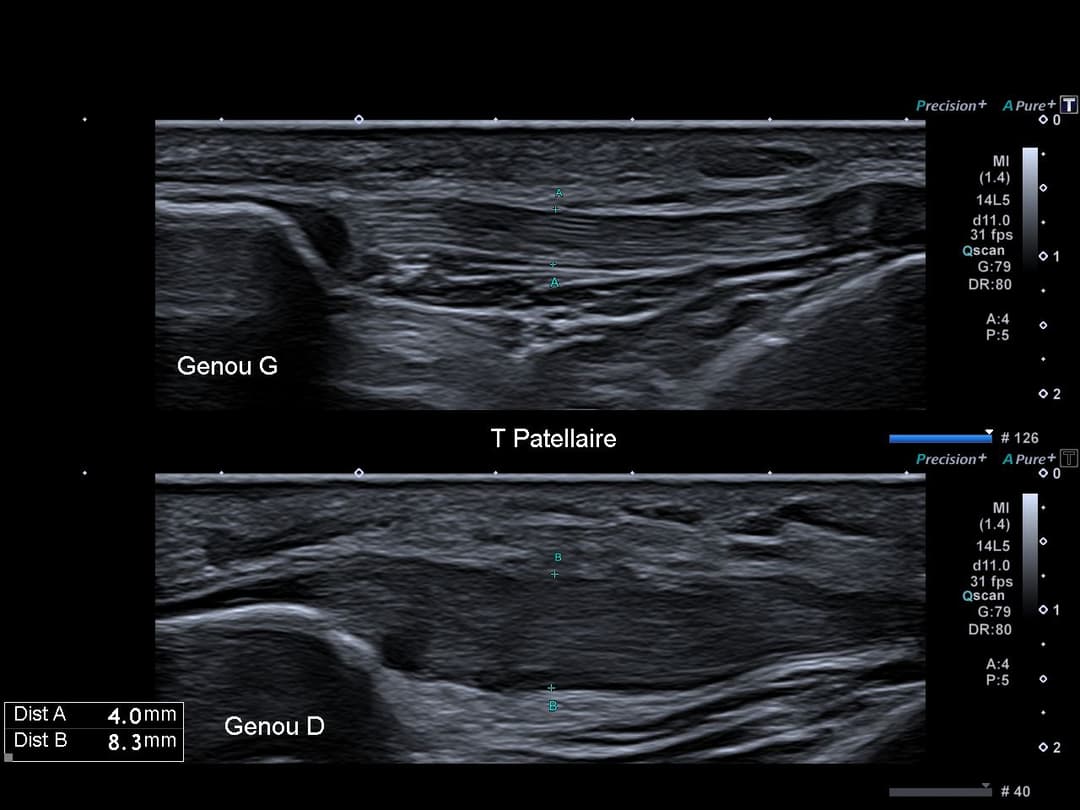

Tendon patellaire présentant un épaississement global et fusiforme de sa portion corporéal, mesurant jusqu’à 8 mm d’épaisseur à droite contre 4 mm à gauche, avec légère perte de son architecture fibrillaire sans fissuration.